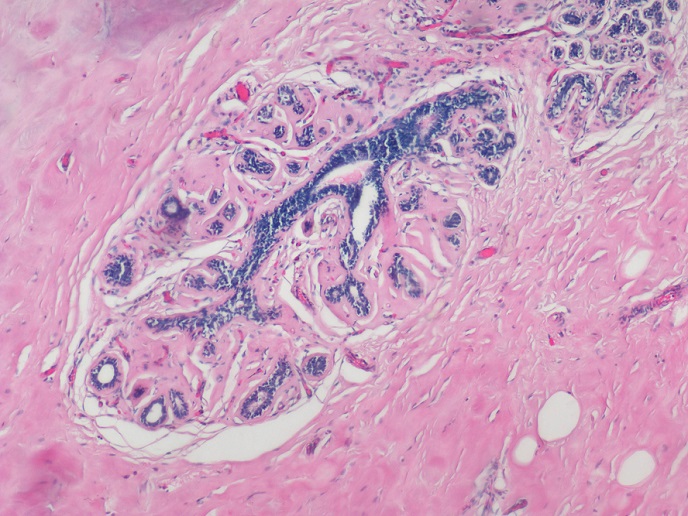

Ã÷ÃĀÉúÎīī@ÎĸįR´îŨd¸ßˇÖąæÂĘMSX2ĪāCŖŦŋÉĮåÎúŗĘŦFHEČžÉĢ˛ĄĀíĮĐÆŦĩÄŧ°ûŧšŖ¨ČįČéĪŲ°ŠĶąžÖĐË{ÉĢĩÄŧ°ûēËÅcŧtÉĢĩÄ°ûŲ|ŖŠŖŦÍÖúŋėËŲ×Re°Šŧ°ûĐÎBĖØÕ÷ŖŦéžĢĘÔ\āĖᚊŋÉŋŋŌĀūĄŖ

Ã÷ÃĀÉúÎīī@ÎĸįR´îÅämsx2ÅÄzHEČžÉĢĩÄČéĪŲ°Š˛ĄĀíĮĐÆŦŖŦŧtÉĢé°ûŲ|ŖŦË{ÉĢéČžÉĢķw